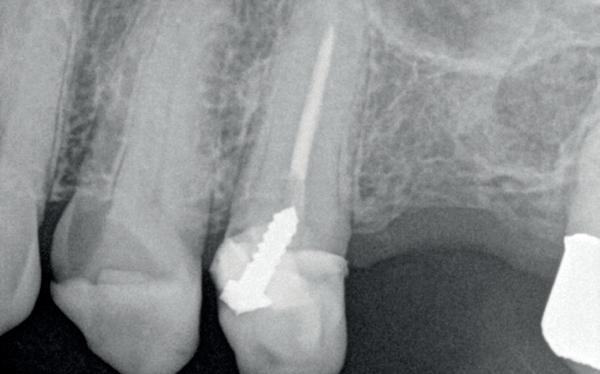

Je kan nu denken, heb ik nu net een gans artikel gelezen van een endodontoloog over hoe ik vooral geen wortelkanaalbehandelingen moet doen? Iemand die zo tegen zijn winkel spreekt kan waarschijnlijk gewoon geen goede wortelkanaalbehandelingen uitvoeren… Deze opmerking heb ik al een aantal keren gehoord wanneer ik een presentatie geef. Meestal begin ik dan ook met het tonen van een zeer uitdagende casus. In dit geval zal ik hetzelfde doen. Foto 1 is een recente wortelkanaalbehandeling die ik uitgevoerd heb. Zowat de natte droom van elke endodontoloog. Nu dat van de baan is, nog enkele voorbeelden uit de praktijk waarbij ik de patiënt centraal heb gezet en soms tegen de vraag van de verwijzende tandarts ben ingegaan.

De verwijzende tandarts wil tanden 24 en 25 overkronen en vraagt evaluatie en eventuele wortel-

kanaalbehandelingen en stiftopbouwen (foto 2). U ziet, mijn verwijzers zijn getraind en vragen eerst een evaluatie of het wel nodig is. Dit heeft me bloed, zweet en tranen gekost, alsook enkele verwijzers. Uiteindelijk bleek tand 24 vitaal te zijn en was er voldoende restweefsel om adhesief te werken. De wortelkanaalbehandeling op de 25 is misschien technisch niet ideaal, maar er zijn geen klachten of radiologische tekenen van infectie. In overleg met de patiënt is dus besloten om tand 24 te voorzien van een stompopbouw en tand 25 van een glasvezelstift en stompopbouw zonder te herbehandelen (foto 3). De tandarts kan onmiddellijk verder met de kronen.

Casus 2

Trauma bij een 11-jarige. Tand 41 was geluxeerd met een beperkte extrusie. Hij reageerde niet op koude en de vraag was om een wortelkanaalbehandeling uit te voeren (foto 4). Bij trauma wordt er echter dikwijls te snel een conclusie getrokken en aangezien er geen

klinische klachten waren, werd besloten om verder op te volgen. Acht maanden later reageren alle tanden vitaal en is tand 41 aan het verkalken. Er is dus geen wortelkanaalbehandeling nodig (foto 5).

Deze 73-jarige man kwam bij mij voor een endodontische behandeling van tand 21. Zijn tandarts was net met pensioen en hij was bij een nieuwe tandarts terechtgekomen. Daar stelde men een zwarting vast en deze zou behandeld moeten worden. De patiënt heeft nooit klachten gehad aan deze tand. De brug zit er al tientallen jaren, ASA 2 met bloedverdunners en een dun biotype qua gingiva met ook al wat recessie aan de kroonrand. Na overleg met de patiënt is besloten om geen slapende honden wakker te maken en de situatie jaarlijks op te volgen met een röntgenfoto (foto 6).

Deze 51-jarige vrouw werd verwezen omwille van pijnklachten met de vraag of een wortelkanaalbehandeling nog mogelijk was, of dat er eerder naar extractie gekeken moest worden (foto 7). De tand testte nog vitaal tijdens de consultatie dus ik besloot om eerst de vulling te verwijderen. Het bleek een typische “cracked tooth” (foto 8-9). Ik besloot om de tand te voorzien van een adhesieve stompopbouw (foto 10). En bij de opvolging zes maanden later (foto 11) was de patiënt al die tijd klachtenvrij en kreeg de tandarts groen licht om verder te gaan met een indirecte restauratie. Geen wortelkanaalbehandeling en al zeker geen extractie nodig.